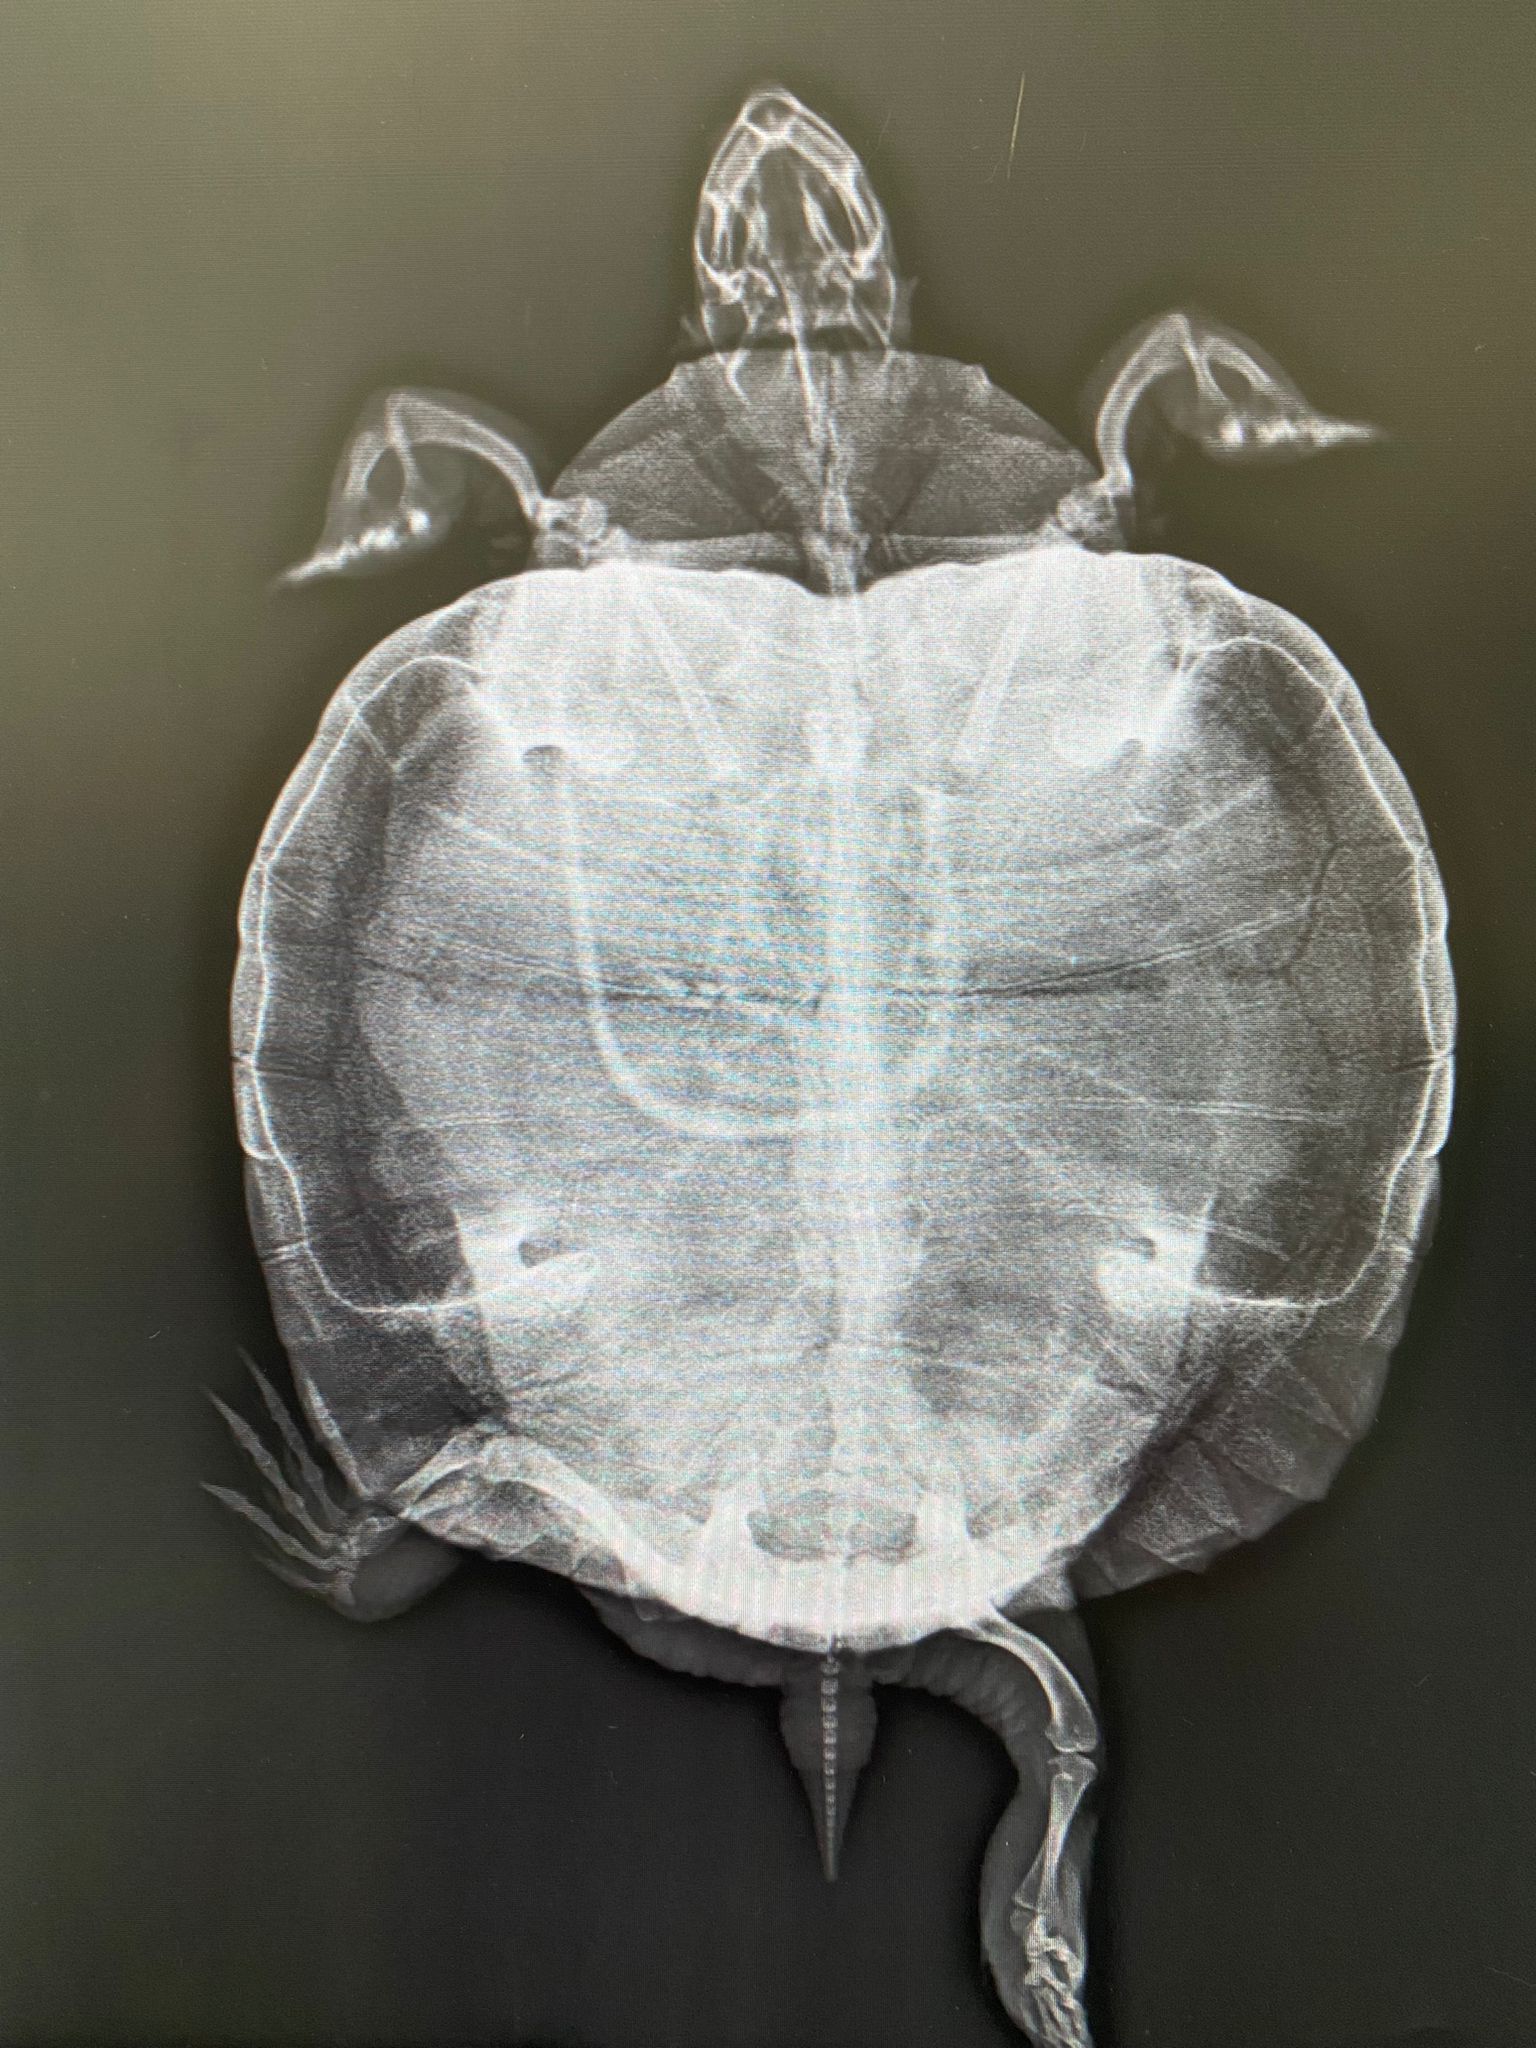

La tortuga de un amigo tiene deformado el caparazón(desde siempre), pondré más abajo alguna foto de como es, pero vamos la deformación que tiene el caparazón como metido hacia dentro y más aplastado.

En la radiografía se le ve bastante falta de calcio.

Me sorprende que las patas traseras no se vean encorvadas como plátano por la descalcificación.